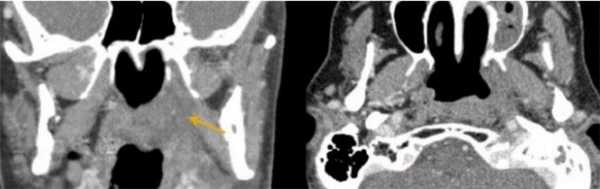

Плоскоклеточный рак на КТ носовых пазух с контрастом. Ткань опухоли отмечена длинной стрелкой, деструктивные изменения кости левого верхнечелюстного синуса - короткой.